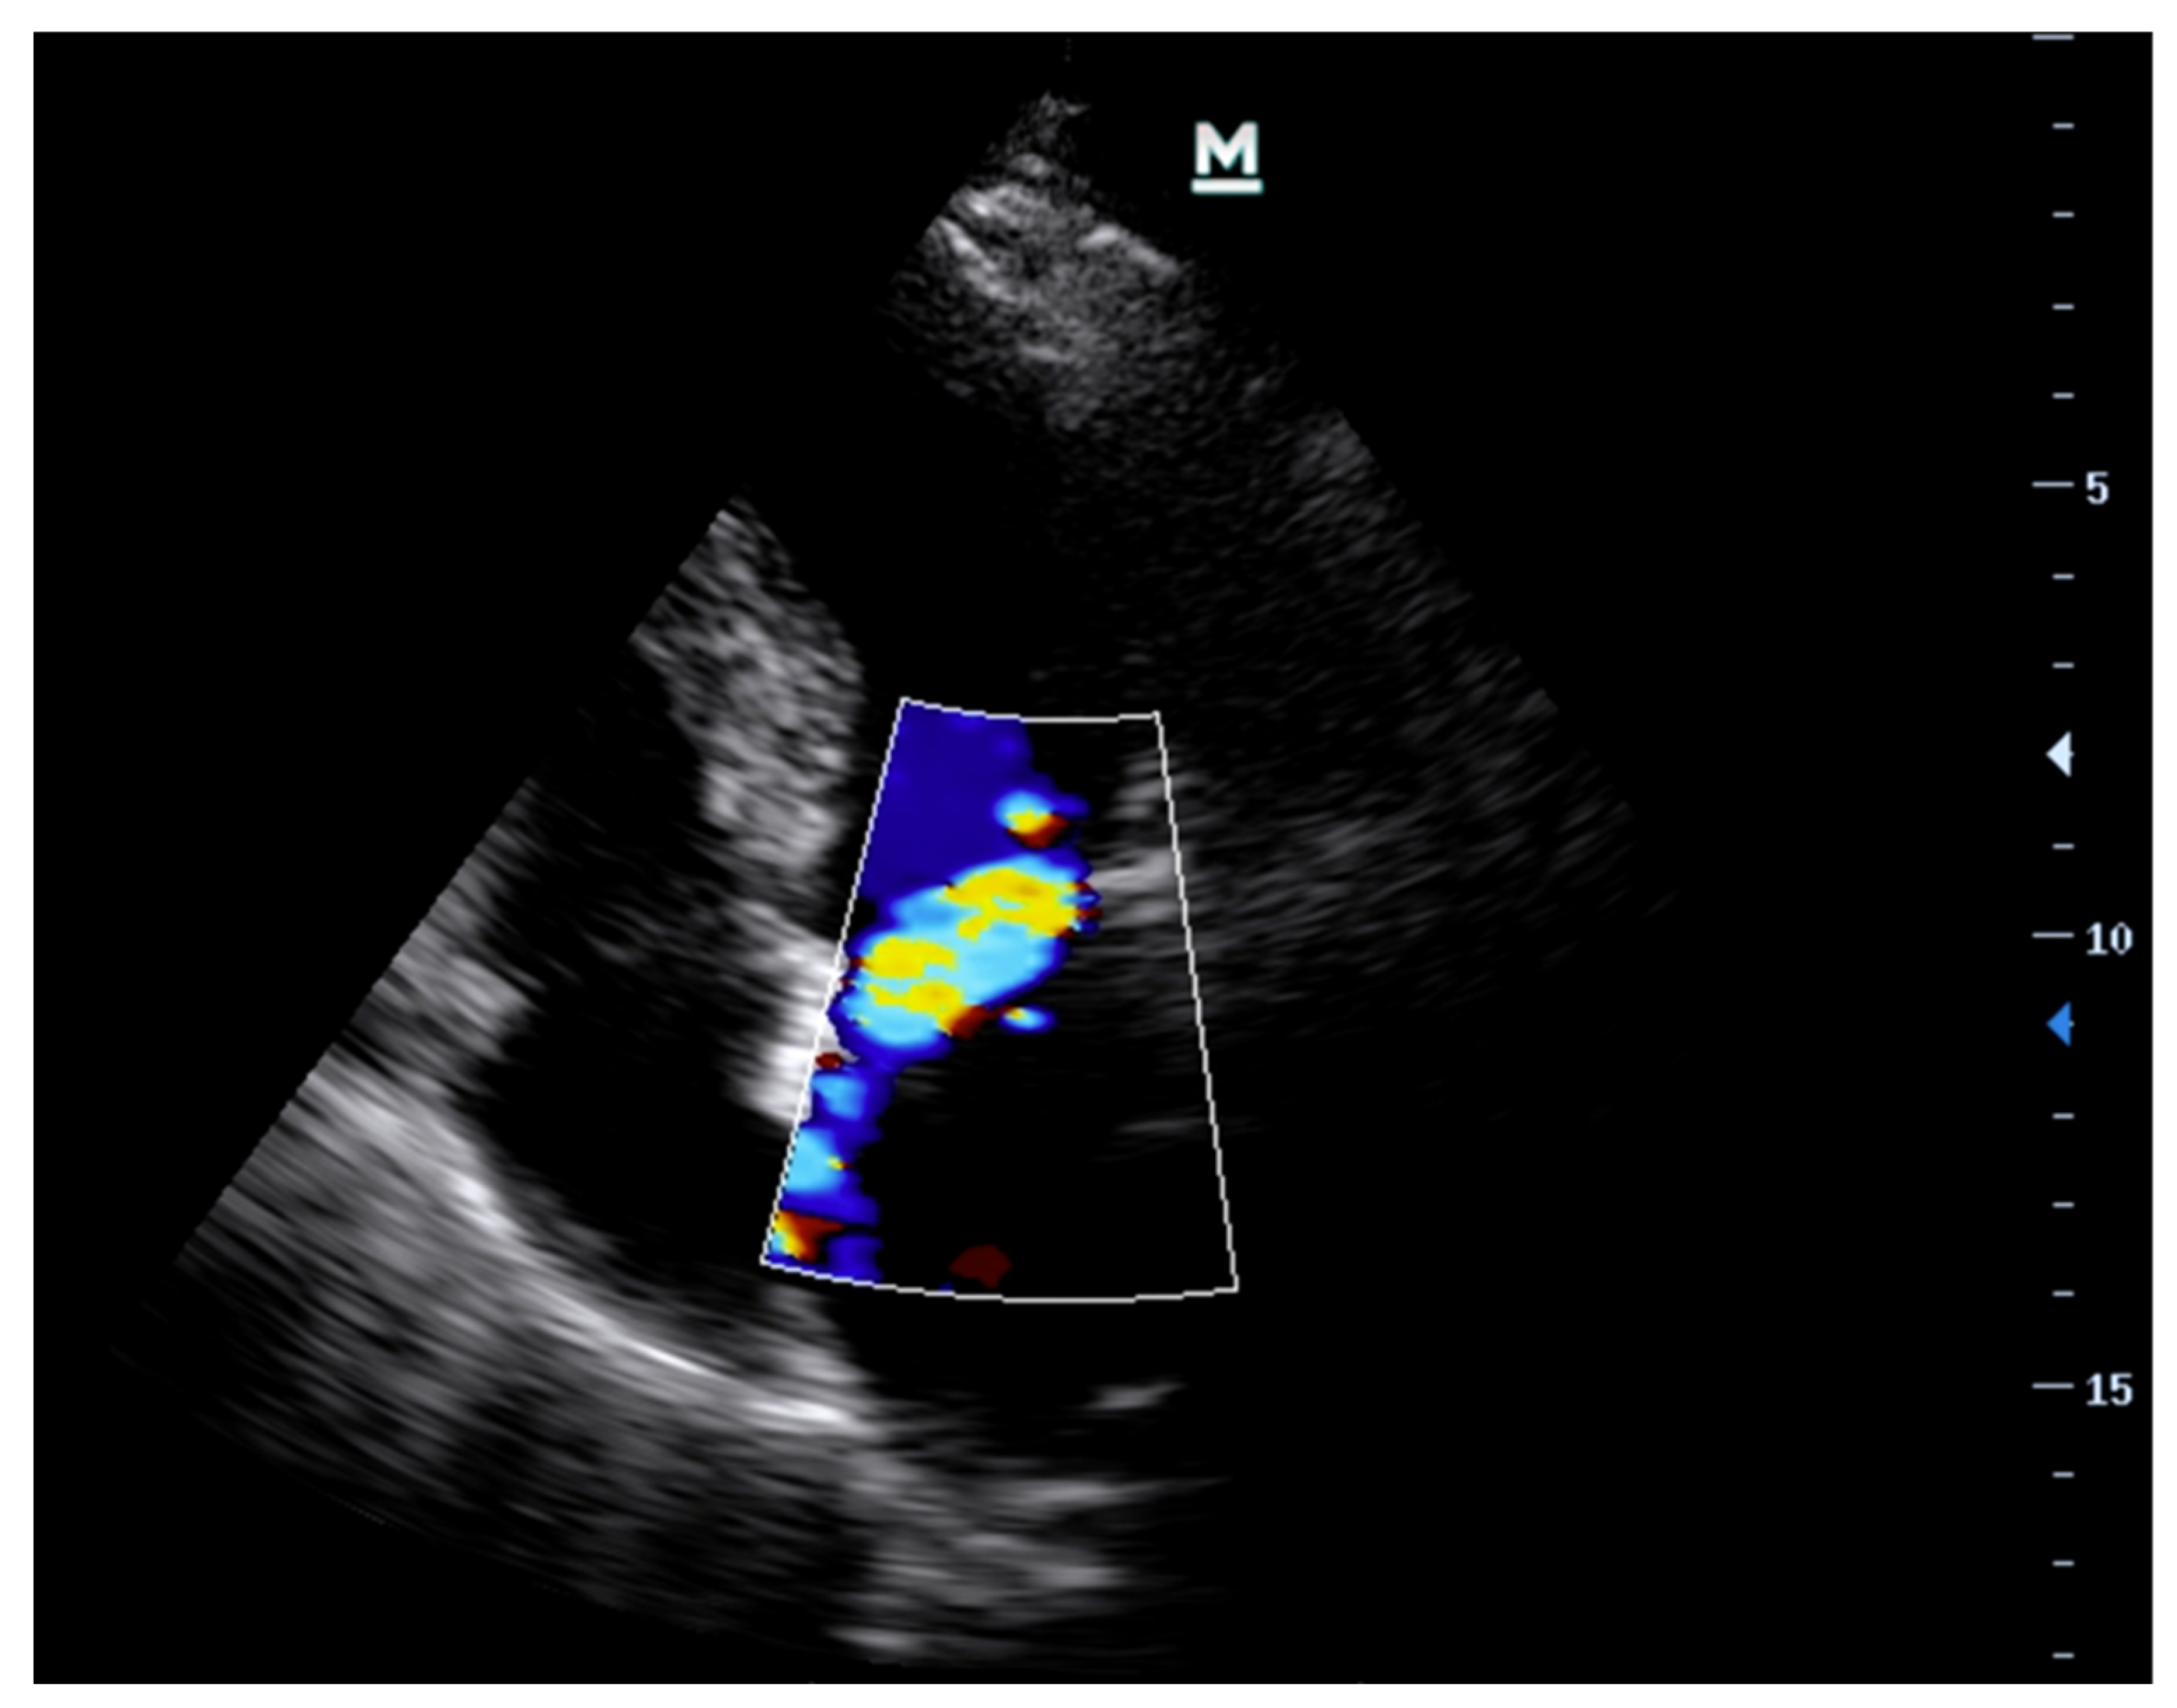

| Colour Flow Doppler (CFD) | Colour flow is not a good marker for assessment of severity of MR or AR. However, it may assist with determining aetiology—usually eccentric jets if prolapse/flail in the direction that is away from the prolapsing/flail leaflet i.e., anterior mitral valve leaflet prolapse leads to a posteriorly directed jet. | Central jet, typically directed towards the posterior wall of the left ventricle. |